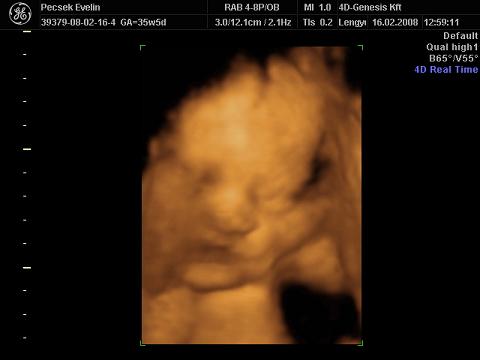

Voltunk 4D-s UH-n is, igaz, hogy 02.16-án (33. héten), de most teszek fel képeket és adatokat a gép hibája miatt

súly: 2211g

BPD: 8,35cm

OFD: 10,62cm

HC:30,3cm (nekem születéskor volt 30cm a fejkörfogatom :shock: )

AC:29,67cm

FL:6,45cm

Liza nőiessége:

ásít, már nagyon únja a banánt :lol: :

itt a nyelvét nyújtogatja:

kezével csikizi a saját kis talpát :lol: :

Liza megmutatta az arcát a végére (egész végig takarta a kezével és lábával, bezzeg a punciját azt nem):